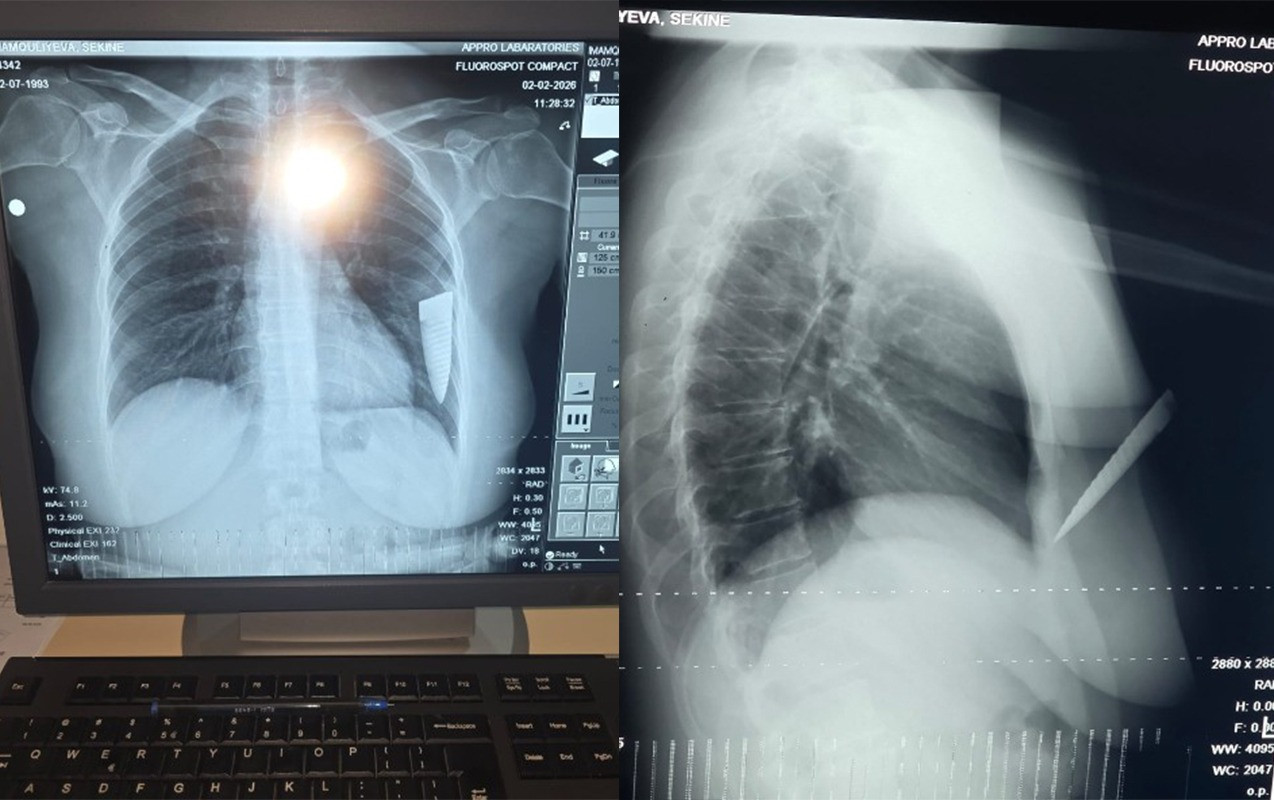

“Hadisə fevralın 1-də saat 19:00 radələrində yaşadığım Gəncə şəhərindən Şəmkirə dəvət edildiyim toy mərasimindən çıxarkən baş verdi. Şadlıq evinin qarşısında maşınıma minərkən əvvəllər qeyri-rəsmi münasibətdə yaşadığım Əli Kamran oğlu Əsgərov qəfil hücum etdi. O, gözlənilmədən maşınıma yaxınlaşdı, sağ ön qapını açaraq boğazımdan tutub boğmağa çalışdı. Daha sonra cibindən bıçaq çıxarıb 4 dəfə zərbə endirdi. Zərbələrdən biri ürək nahiyəmə, üçü isə sol qoluma dəydi. Həmin vaxt bıçaq qırılaraq döş qəfəsimdə qaldı, yoxsa daha çox zərbə endirib məni öldürə də bilərdi, çünki bıçaqla ardıcıl olaraq məni vururdu. Bıçağın qırıldığını, ətrafdakı insanların səs-küyə gəldiyini görərək qaçıb getdi”, - şikayətçi bildirib.

S.İmamquliyeva qeyd edib ki, hadisəyə səbəb onun sevgilisindən ayrılması olub: “Artıq münasibətimiz bitmişdi. Əli Əsgərov ayrılıqdan sonra məni mütəmadi izləyir, hədə-qorxu gəlirdi. Məni bıçaqlayandan sonra Şəmkir Rayon Mərkəzi Xəstəxanasına, oradan isə Gəncə Beynəlxalq Xəstəxanasına aparılaraq əməliyyat olundum. Döş qəfəsimdə qırılıb qalan bıçağın kəsici hissəsi əməliyyatla bədənimdən xaric edildi. Hazırda səhhətimdə yaranmış ağır fəsadlar səbəbindən işləyə bilmirəm. Bu hadisəyə görə külli miqdarda maddi-mənəvi zərərlə üzləşmişəm, qarşı tərəf isə heç maraqlanmır. Hadisəni törədən şəxsin saxlanıldığı bildirilsə də, istintaqın gedişindən də məlumatsızam. Qarşı tərəf imkanlıdır və təsir imkanları çoxdur. Həyatıma hər an təhlükə ola bilər. Bu işin ədalətli araşdırılmasını və təhlükəsizliyimin təmin olunmasını istəyirəm”.